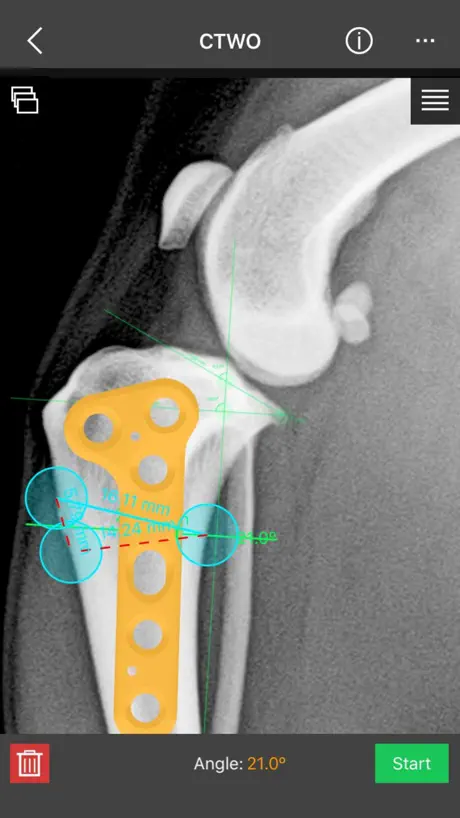

This is a useful tool for traumatology and orthopaedic surgical planning veterinary, including advanced techniques for treat canine anterior cruciate ligament (ACL) injuries (TPLO and CTWO).

e) Wedge cut, CTWO and angular osteotomies.

l) CTWO plates

This is a useful tool for traumatology and orthopaedic surgical planning veterinary, including advanced techniques for treat canine anterior cruciate ligament (ACL) injuries (TPLO and CTWO).

e) Wedge cut, CTWO and angular osteotomies.

l) CTWO plates